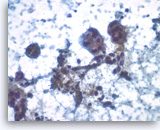

Acinar cell carcinoma,

Pancreas FNA, Cell Block.

The tumor cells are focally positive for chymotrypsin.

40X

Acinar cell carcinoma,

Pancreas FNA, Cell Block.

The tumor cells are focally positive for chymotrypsin.

40X